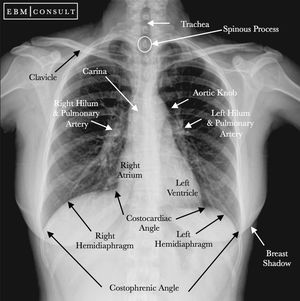

What we can see in a normal CXR